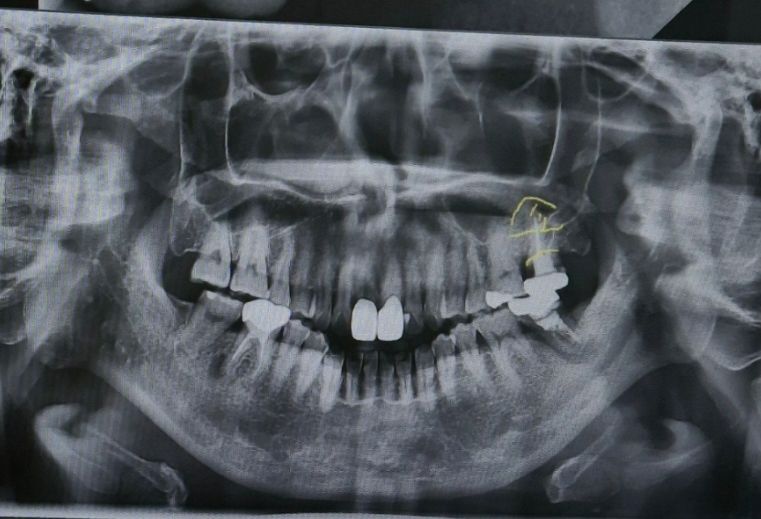

제 사진을 첨부합니다.

사진에 보이는 노란색 선 위아래 발치했습니다.

• 1번 째 사진